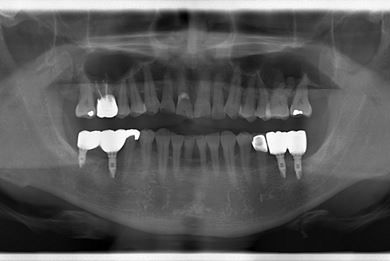

抜歯即日スピードインプラント治療+セラミック治療+歯肉遊離移植術

| 主訴 | 左最奥の下部ブリッジが不安定になっており、奥2本のインプラントを考えたい。 | ||||||||||||||||||||||||||||||||

| 治療方針 | 抜歯と同時にインプラント埋入を行い、治療期間を短縮する。 | ||||||||||||||||||||||||||||||||

| 治療内容 | インプラント4本(抜歯即日スピードインプラント)、メタルボンドセラミッククラウン5本、ハイブリッドセラミッククラウン1本(ハイブリッドセラミック用土台1本) | ||||||||||||||||||||||||||||||||

| 治療期間 | 1年2ヶ月 |